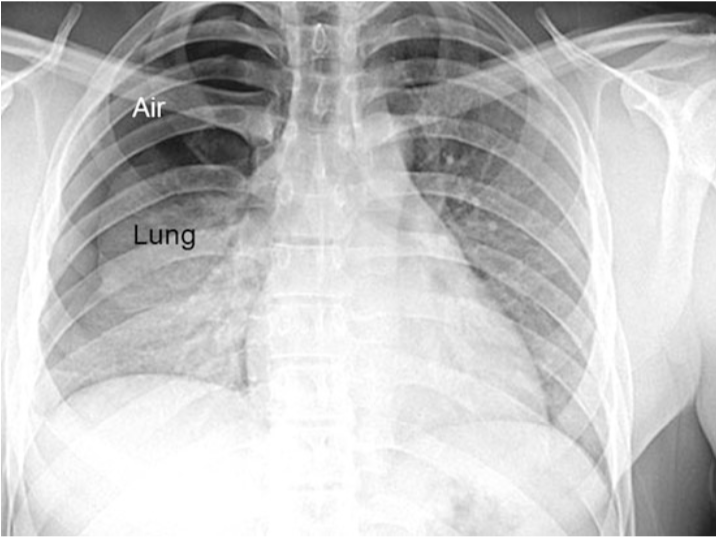

What type of atelectasis is this?

Relaxation (Pneumothorax)